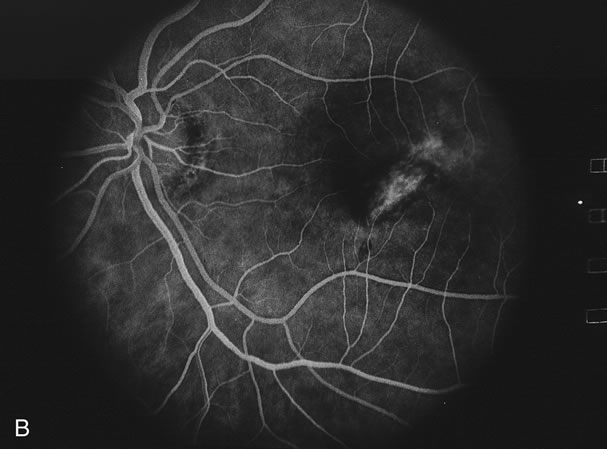

Classically, there are broad areas of chorioretinal atrophy that may take a jigsaw pattern. Usually the atrophy is centered on the disc and spreads along the vascular arcades and then towards the fovea. Sometimes the choroiditis starts within the macula and spreads out from there. Both eyes tend to be affected although there may be marked asymmetry between the two eyes. The active disease appears as yellow-gray areas. If there is evidence of previous disease, then the active areas tend to be at the edge of the chorioretinal atrophy (Figs. 16 to 18). Rarely, there may be several noncontiguous areas of chorioretinal atrophy in the eyes. Retinal vasculitis at the site of an active lesion and retinal vein occlusions may rarely be seen.

Fig. 16. A. Color fundus photograph showing the jigsaw pattern of choroidal and retinal atrophy extending from the disc along the arcades. At the inferior edge of the superotemporal lesion there is a recurrence noted by the grayness of the retina. B. Fluorescein angiogram in the laminar venous phase showing a large window defect in the area of inactive choroiditis and blockage of the choroidal fluorescence in the area of active choroiditis. C. In the late phase of the fluorescein angiogram there is staining of the edges of the inactive choroiditis and marked hyperfluorescence in the area of active choroiditis.

Fig. 17. A. Classic inactive case of serpiginous choroiditis showing the jigsaw pattern of disease surrounding the fovea. B. Fluorescein angiogram showing staining of the edges of the inactive serpiginous choroiditis. There is blocked fluorescence in the areas of hyperplasia of the retinal pigment epithelium. C. Indocyanine green angiogram showing absence of fluorescence in the area of inactive choroiditis.